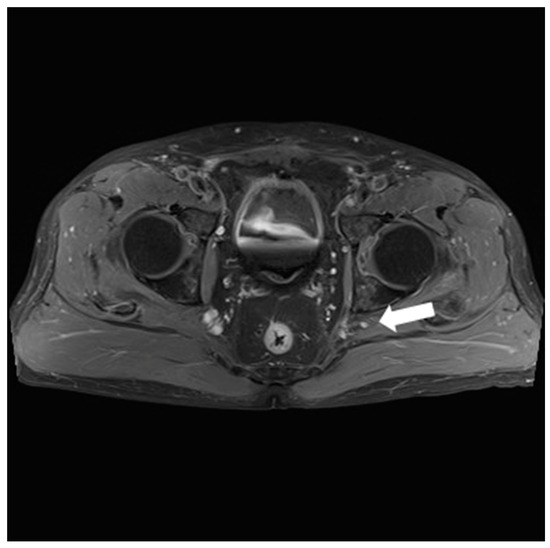

2.1. Preoperative Evaluation